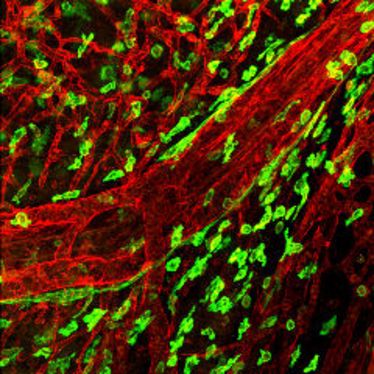

Vortrag des SFB 492: Extrazelluläre Matrix

Vortrag des SFB 492: Extrazelluläre Matrix

SFB492-Kolloquium

SFB492-Kolloquium

SFB492-Kolloquium:

SFB492-Kolloquium:

SFB492-Kolloquium:

SFB492-Kolloquium:

SFB492-Kolloquium:

SFB492-Kolloquium:

SFB492-Kolloquium

SFB492-Kolloquium

First SmArt Workshop on Extracellular Matrix of the Vessel Wall

First SmArt Workshop on Extracellular Matrix of the Vessel Wall

SFB492-Kolloquium: Molecular and functional analysis of vascular receptor tyrosine kinase signaling

SFB492-Kolloquium: Molecular and functional analysis of vascular receptor tyrosine kinase signaling